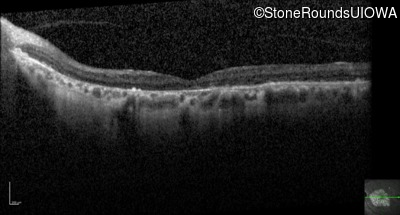

Optical Coherence Tomography - Right - 20/200 sc

Exemplar / OCT Stack

OCT Stack